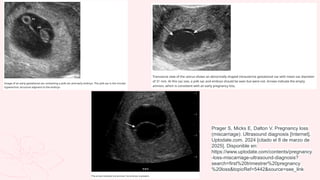

Prager S, Micks E, Dalton V. Pregnancy loss

(miscarriage): Ultrasound diagnosis [Internet].

Uptodate.com. 2024 [citado el 8 de marzo de

2025]. Disponible en:

https://www.uptodate.com/contents/pregnancy

-loss-miscarriage-ultrasound-diagnosis?

search=first%20trimestrer%20pregnancy

%20loss&topicRef=5442&source=see_link

HC y exploración física Especuloscopía A USG endo/abdominal Deberepetirse 7-10 días despues para valorar viabilidad/explusión de restos Diagnóstico 4 B >1500mUI se puede ver el saco gestacional/ saco vitelino visible hasta las 5.5SDG/ Actividad cardíaca fetal 6-6.5SDG Guía de Práctica Clínica Diagnóstico y Tratamiento del Aborto Espontáneo, Manejo Inicial de Aborto Recurrente IMSS-088-08, México; Instituto Mexicano del Seguro Social, 2009. Disponible en: https://www.imss.gob.mx/sites/all/statics/guiasclinicas/088GER.pdf

Prager S, MicksE, Dalton V. Pregnancy loss (miscarriage): Ultrasound diagnosis [Internet]. Uptodate.com. 2024 [citado el 8 de marzo de 2025]. Disponible en: https://www.uptodate.com/contents/pregnancy -loss-miscarriage-ultrasound-diagnosis? search=first%20trimestrer%20pregnancy %20loss&topicRef=5442&source=see_link

• #15 Aborto diferido: imagen superior izquierda: al doppler color no se aprecia vascularidad y no hay FCF Imagen superior derecha: restos ovulares Imagen inferior izquierda: aborto en evolución, se ve apertura cervical y presencia de saco